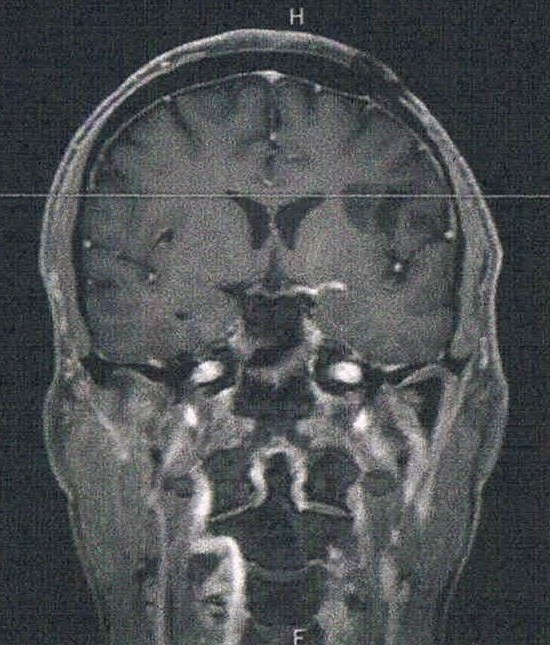

- MRI検査: 造影剤なし /

造影剤あり 造影剤ありの場合:4時間前から絶食し、MRIの1時間前に血液検査を済ませる。

- 造影剤の有無でも見え方が違うのかもしれないが、上下方向は明らかに大きくなっている。玉子で例えると、直径は変わらないが上下が大きくなっている。